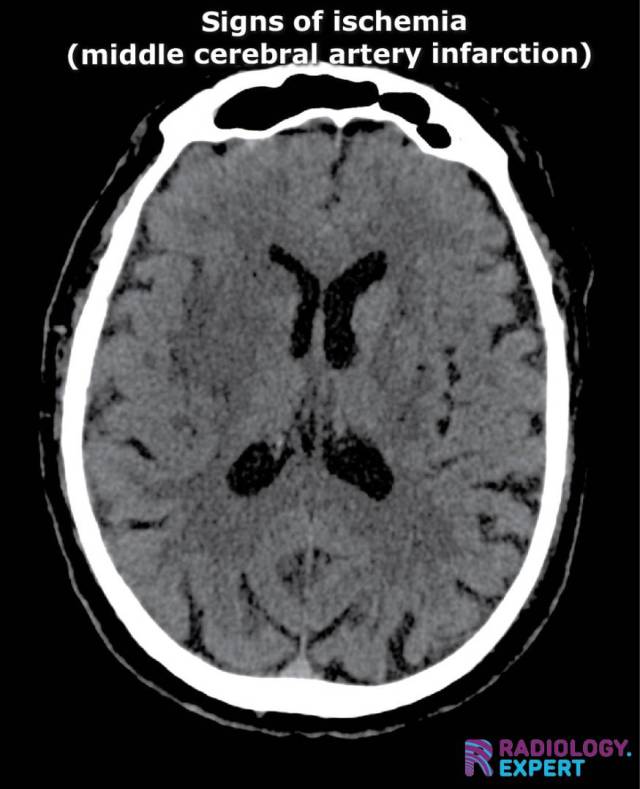

ischemic sigs MCA infarction on CT. Insular ribbon sign. Blurring basal ganglia ischemic sigs MCA infarction on CT. Insular ribbon sign. Blurring basal ganglia

Click image to see overlay